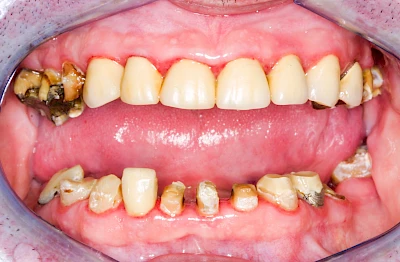

Ist zunächst nur das Zahnfleisch von der Entzündung betroffen, spricht man von Gingivitis. Später, wenn auch der Knochen um die Zähne herum entzündet ist, spricht man von einer Parodontitis. Bei der Parodontitis wird der Knochen nach und nach abgebaut und das Zahnfleisch zieht sich zurück. Die Zahnhälse und Zahnwurzeloberflächen liegen mehr und mehr frei. Die Zähne werden zunehmend lockerer und fallen schließlich aus.

Bakterien in den Zahnbelägen greifen neben den Zähnen auch das Zahnfleisch (Gingiva) und den gesamten Zahnhalteapparat (Parodont) an. Der Körper reagiert mit einer Entzündung, sichtbar als Rötung und Schwellung. Meist blutet das Zahnfleisch z .B. beim Essen oder auch beim Putzen der Zähne.